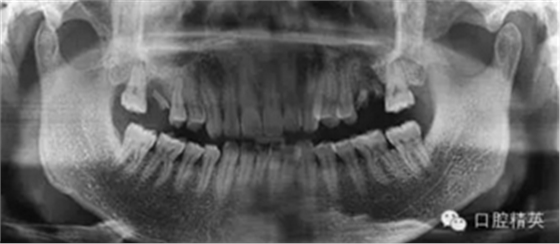

拔除前曲断

X线显示左上颌6残根,慢性根尖周围炎波及上颌窦底,行拔除残根处理,嘱术后常规消炎。